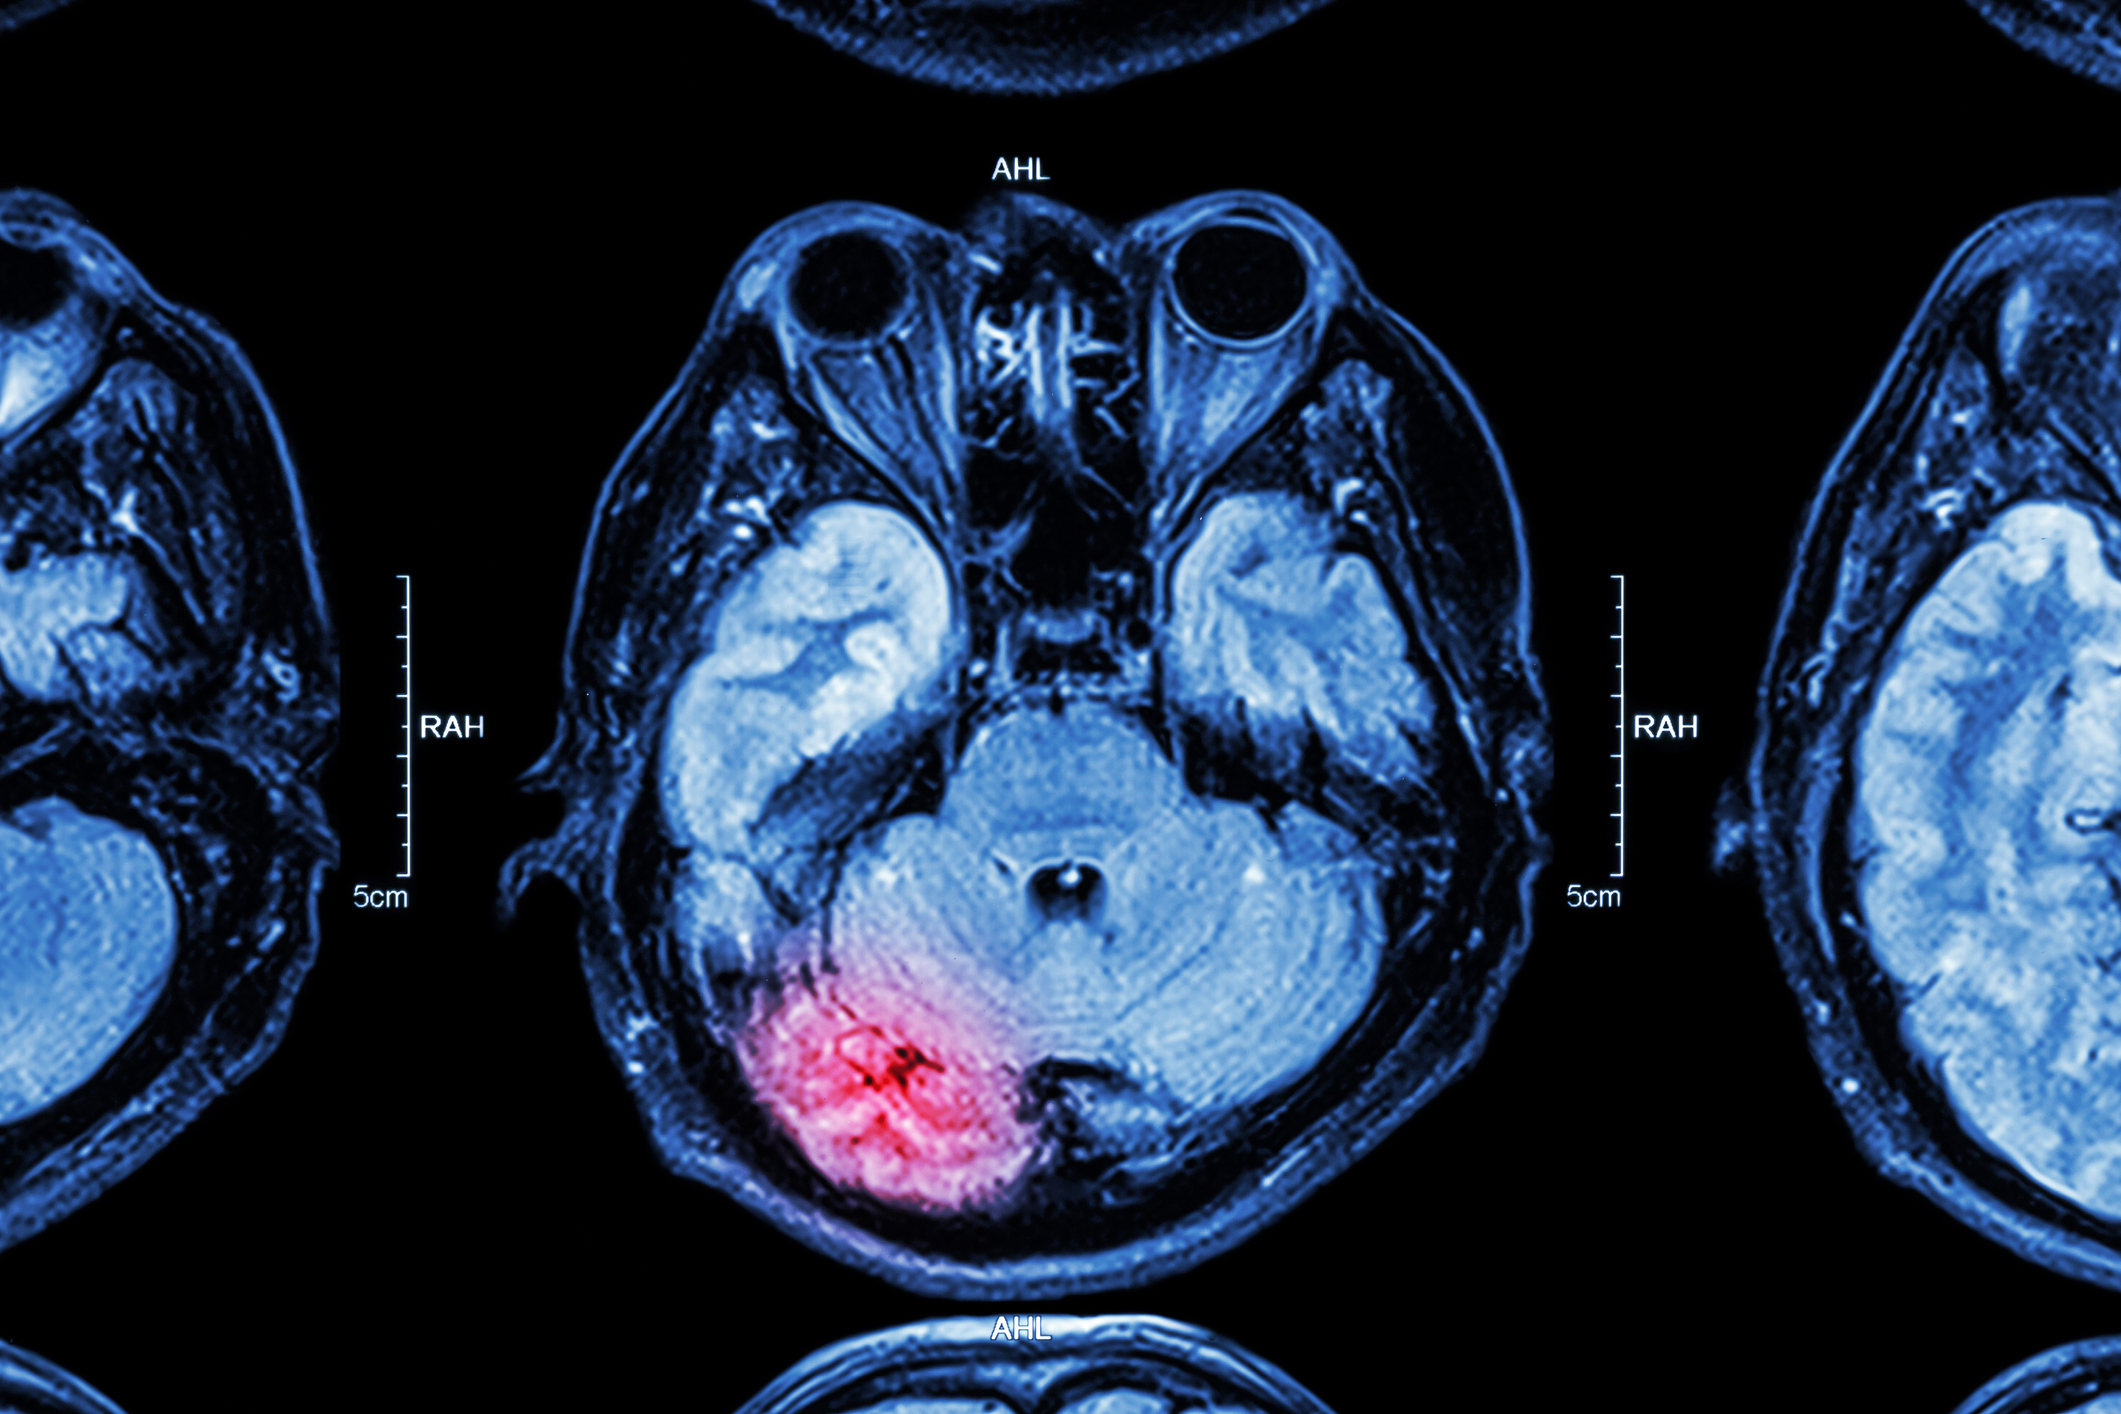

According to the Centers for Disease Control and Prevention, these could all be symptoms of a Traumatic Brain Injury, or TBI. While these types of injuries most often come up in the context of professional football players and military personnel sustaining concussions, there’s a third group that disproportionately suffers from TBIs — female survivors of intimate partner violence, or IPV. The little — but influential— research that’s been done on this demographic indicates that it could account for the majority of TBI sufferers in the U.S. However, IPV survivors have been marginalized in TBI research.

Because Valera’s primary funding came from the ADHD research, it took some time for her to get the TBI data analyzed. Her research, which finally published in 2017, indicated that IPV survivors who’d suffered from TBIs had “poorer cognitive performance” when it came to both memory and learning.

Van Donkelaar pivoted his studies, and the pair started SOAR, Supporting Survivors of Abuse and Brain Injury through Research. Through their work, Van Donkelaar says he’s found that IPV survivors “had more, and more severe, symptoms than the young athletes” he’d studied. Furthermore, he was testing the IPV survivors about a year after their most recent brain injury, while he’d been looking at young athletes within three days of theirs. That meant IPV survivors’ TBI symptoms were “chronic in nature,” he says. Like in Valera’s studies, he found cognitive functioning in these survivors had been negatively affected.